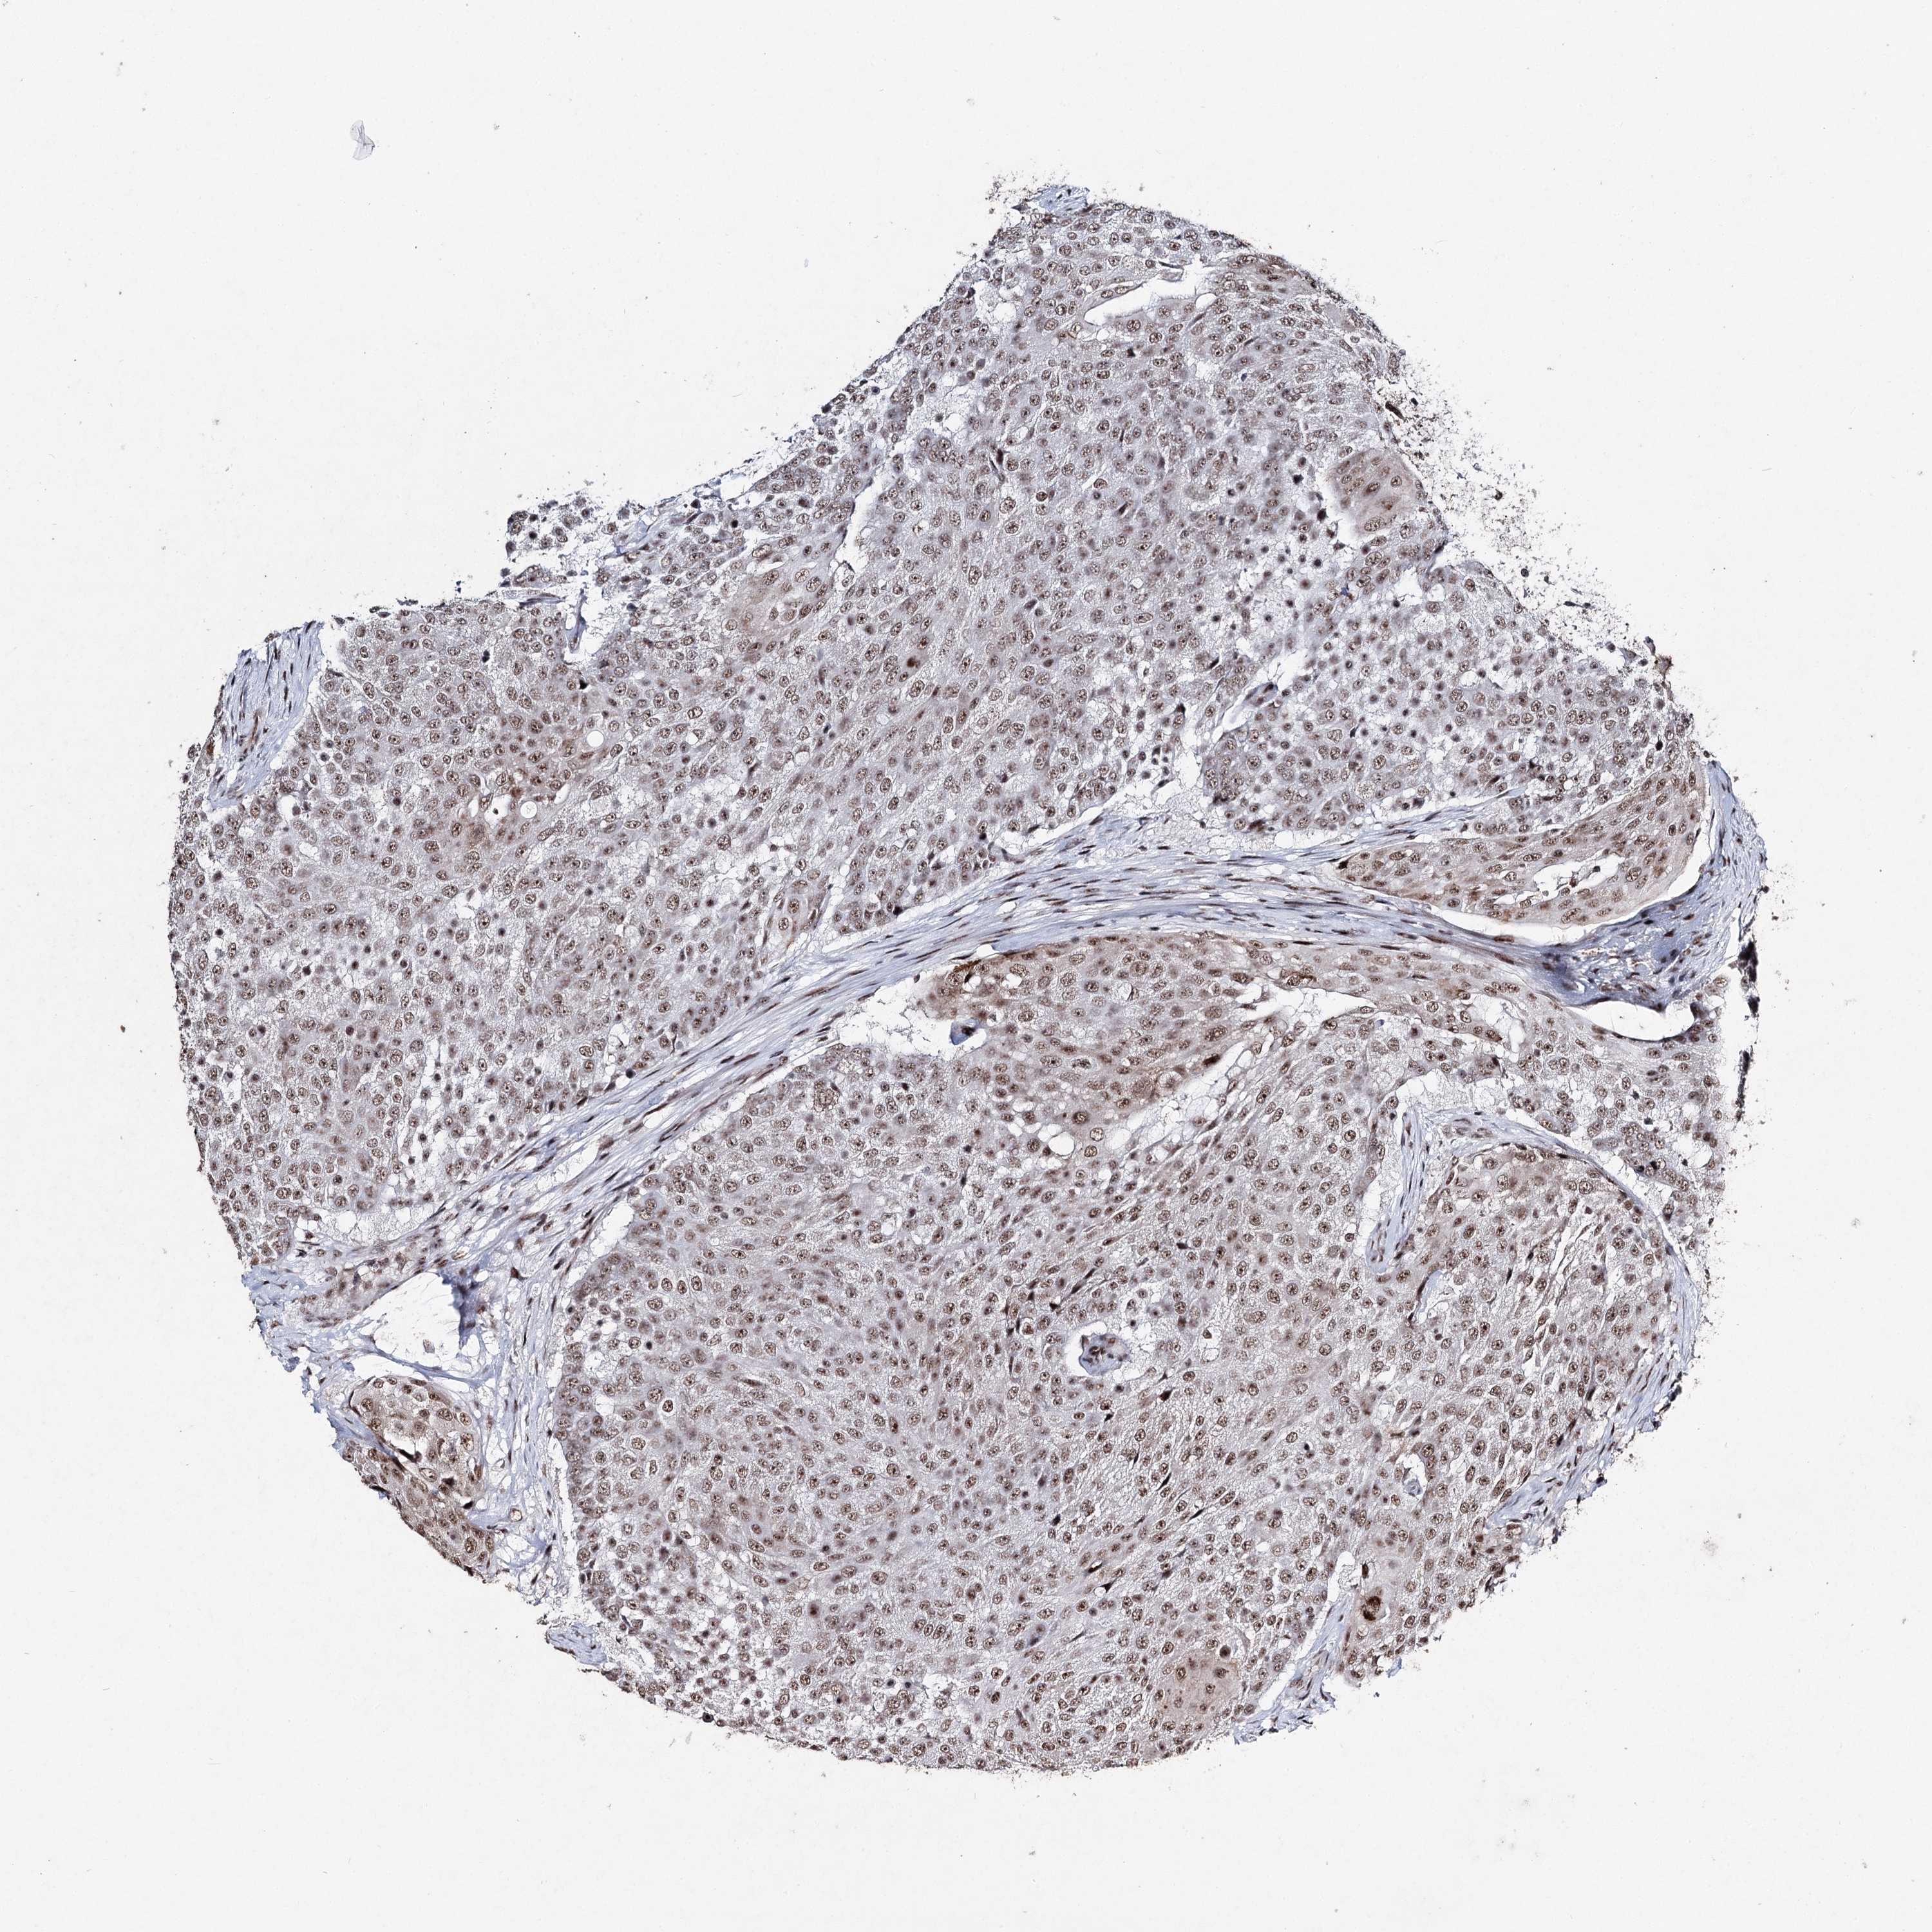

UROTHELIAL CANCER - Protein expressioni

A mouse-over function shows sample information and annotation data. Click on an image to view it in a full screen mode. Samples can be filtered based on level of antibody staining by selecting one or several of the following categories: high, medium, low and not detected. The assay and annotation is described here.

Note that samples used for immunohistochemistry by the Human Protein Atlas do not correspond to samples in the TCGA dataset.

Antibody stainingi

Antibody staining in the annotated cell types in the current human tissue is reported as not detected, low, medium, or high, based on conventional immunohistochemistry profiling in selected tissues. This score is based on the combination of the staining intensity and fraction of stained cells.

Each image is clickable and will lead to virtual microscopy that enables deeper exploration of all samples and also displays staining intensity scores, fraction scores and subcellular localization as well as patient and tissue information for each sample.

Antibody HPA001032

Antibody HPA027214

Antibody CAB037024

Staining

High

Medium

Low

Not detected

Intensity

Strong

Moderate

Weak

Negative

Quantity

>75%

75%-25%

<25%

None

Location

Nuclear

Cytoplasmic/membranous

Cytoplasmic/membranous,nuclear

Urothelial carcinoma, High grade

Urothelial carcinoma, Low grade

Urothelial carcinoma, NOS